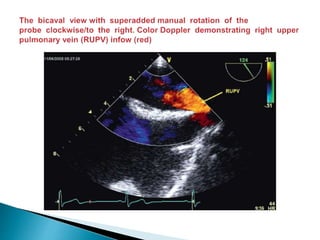

 Evaluation of the right sided veins is usually straight forward.

 From the mid esophageal 4 chambers view the probe is rotated to the right (with the

image sector angle at 0–30° and depth at about 10 cm) such that the inter-atrial septum is

horizontal and in the centre of the screen .

 Color Doppler is added to the left side of the screen and the probe is advanced slowly

until 2 distinct pulmonary infows are seen ; the more horizontal flow is from the RLPV and the

more vertical fow is from the RUPV.

 The RUPV can also be seen by maintaining the probe depth, rotating the image sector

plane to the bicaval view at 80–120° , and then manually rotating the probe clockwise/to the

right .

 This latter view of the RUPV is especially useful in patients’ with atrial septal defects (ASD)

when excluding anomalous pulmonary venous drainage (most commonly the RUPV) and

when assessing the distance betweenthe rim of the ASD and the RUPV prior to considering

percutaneous closure.